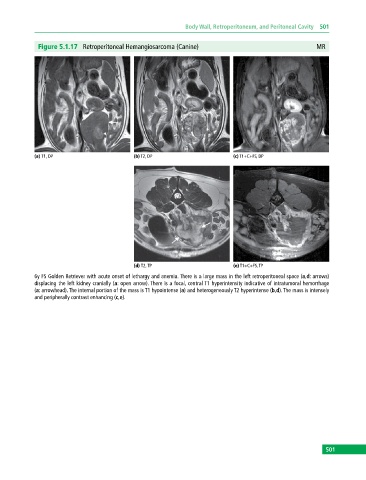

Figure 5.1.17 Retroperitoneal Hemangiosarcoma (Canine) MR

(a) T1, DP (b) T2, DP (c) T1+C+FS, DP

(d) T2, TP (e) T1+C+FS, TP

6y FS Golden Retriever with acute onset of lethargy and anemia. There is a large mass in the left retroperitoneal space (a,d: arrows)

displacing the left kidney cranially (a: open arrow). There is a focal, central T1 hyperintensity indicative of intratumoral hemorrhage

(a: arrowhead). The internal portion of the mass is T1 hypointense (a) and heterogeneously T2 hyperintense (b,d). The mass is intensely

and peripherally contrast enhancing (c,e).